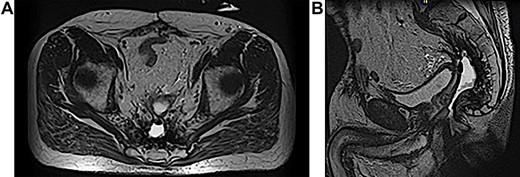

A 63-year-old male presented to the Colorectal Surgery Clinic complaining of constant sanguineous, mucous drainage from a chronic perineal sinus tract. He has a history of T2N1 rectal cancer status post neoadjuvant chemoradiation followed by low anterior resection 17 years prior to presentation complicated by a chronic anastomotic leak. Management of the anastomotic leak required a transverse loop colostomy with subsequent takedown and creation of a diverting loop ileostomy. One year prior to presentation, he underwent exploratory laparotomy with total proctocolectomy and abdominoperineal resection for simultaneous distal loop ileostomy stricture and a stricture at the low anterior resection anastomosis with chronic anastomotic leak, rectal bleeding and mucus drainage. Biopsies were taken at that time given concern for pelvic recurrence which showed benign lymph nodes, fat necrosis and abscess. Since surgery, the patient reported bleeding from a perineal wound and constant passage of mucus. Magnetic resonance imaging (MRI) 1 month prior to clinic presentation showed a retained 2–3 cm sinus cavity in the pelvis with a connecting tract to the perineum (Fig. 1A and B). Exam in clinic revealed a perineal wound with a sub-centimeter cutaneous opening and scant mucous drainage (Fig. 2). Given the MRI findings and significant lifestyle disturbances caused by the chronic drainage, he was scheduled for an exam under anesthesia with endoscopic cauterization of the sinus cavity lining in hopes of obliterating the cavity epithelium.

(A and B) MRI abdomen and pelvis demonstrating 2–3 cm pelvic sinus cavity with connecting tract to the perineum.